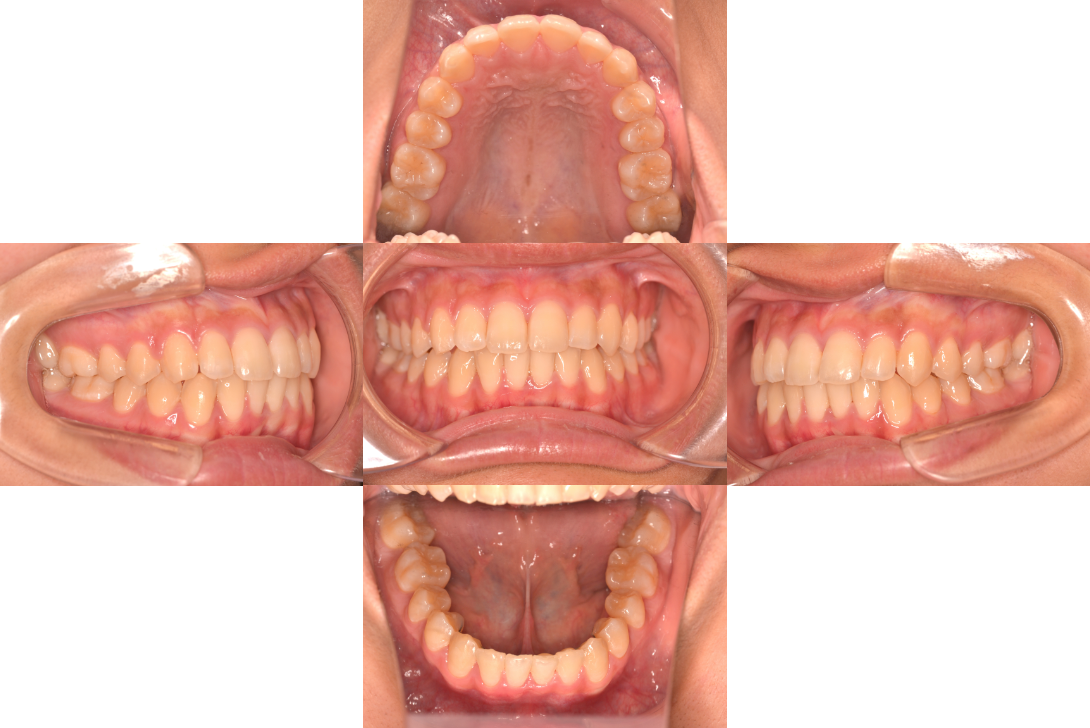

叢生をフルDBSで改善した症例

※DBSとはダイレクトボンディングシステムと呼ばれており、ブラケットにワイヤーを通して歯を動かしていく矯正治療です。

患者情報

18歳女性

主訴

歯並びがガタガタ

行った治療内容

フルDBS

治療のリスク

歯肉退縮、歯根吸収

治療期間

動的治療期間2年4か月

※ クリックして拡大することができます。